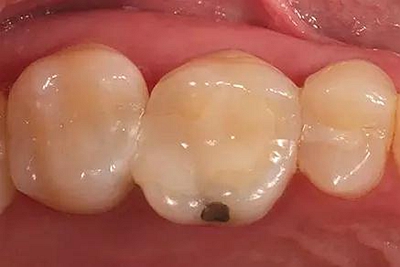

步驟1 原始狀況

16牙位牙齒牙合面觀.

牙齒經過根管治療且充填修補,需要重新修復。